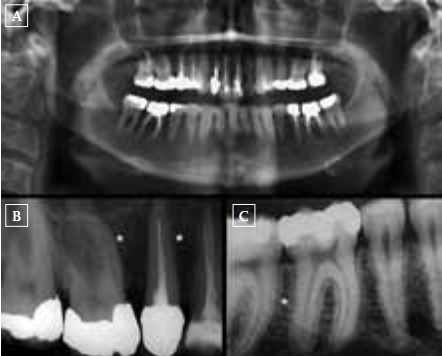

In March 2011, a previously healthy 50-year-old woman underwent an apicotomy (#36) and extraction of two elements (#15, 47) because of progressive mandibular bone resorption and radix fractures. Orthopantomogram (figure 1A) and dental X-ray (figures 1B and C) showed radiolucent spots and loss of the lamina dura, suggesting bone resorption and/or inflammation. Histopathological examination was consistent with undermining bone resorption, showing polynuclear osteoclast-like giant cells and mononuclear fibroblast-like cells, findings associated with either a giant cell granuloma or hyperparathyroidism. As endocrine work-up revealed a parathyroid hormone (PTH) serum level of 88.4 pmol/l (reference 0.6 to 6.7 pmol/l) and a normal calcium level of 2.46 mmol/l (reference 2.20 to 2.60 mmol/l, albumin 43 g/l), the patient was referred to the Outpatient Clinic of Endocrinology. Further analysis showed low 25-hydroxy-vitamin D (25-OHD) of 23 nmol/l (reference 75 to 250 nmol/l), elevated serum creatinine compared with a measurement in 2009 (122 and 74 mmol/l, respectively), and a normal phosphate level of 0.76 mmol/l.

Figure lA-C. (A) Patient's orthopantomogram with periapical bone loss at the first left lower molar (#36) and severe periodontal bone loss at the right lower molar region. (B) One of the patient's dental X-rays (right upper premolars and molars) showing loss of the lamina dura (^^white asterisk), if compared to the dental X-ray of a normal situation (figure 1C, white asterisk). Loss of lamina dura is a manifestation of hyperparathyroidism